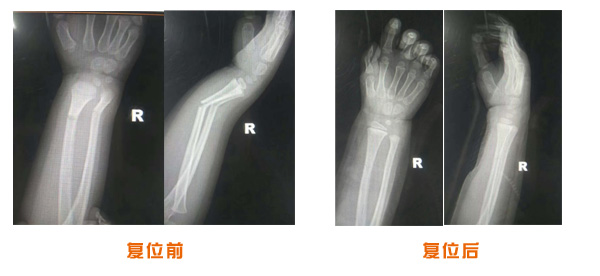

肥城市安駕莊梁氏骨科醫院是一所以梁氏手法正骨配合膏藥為特色的現代化專科醫院。

梁氏骨科術始創于清雍正年間,歷經八代,至今已有三百年歷史。據1929年泰安縣志載“梁瑞圖先生,字增生,號蓮峰,安駕莊人,精岐黃并發明接骨,凡跌打車凡跌打車軋皮不破而碎骨者......【詳細】 |